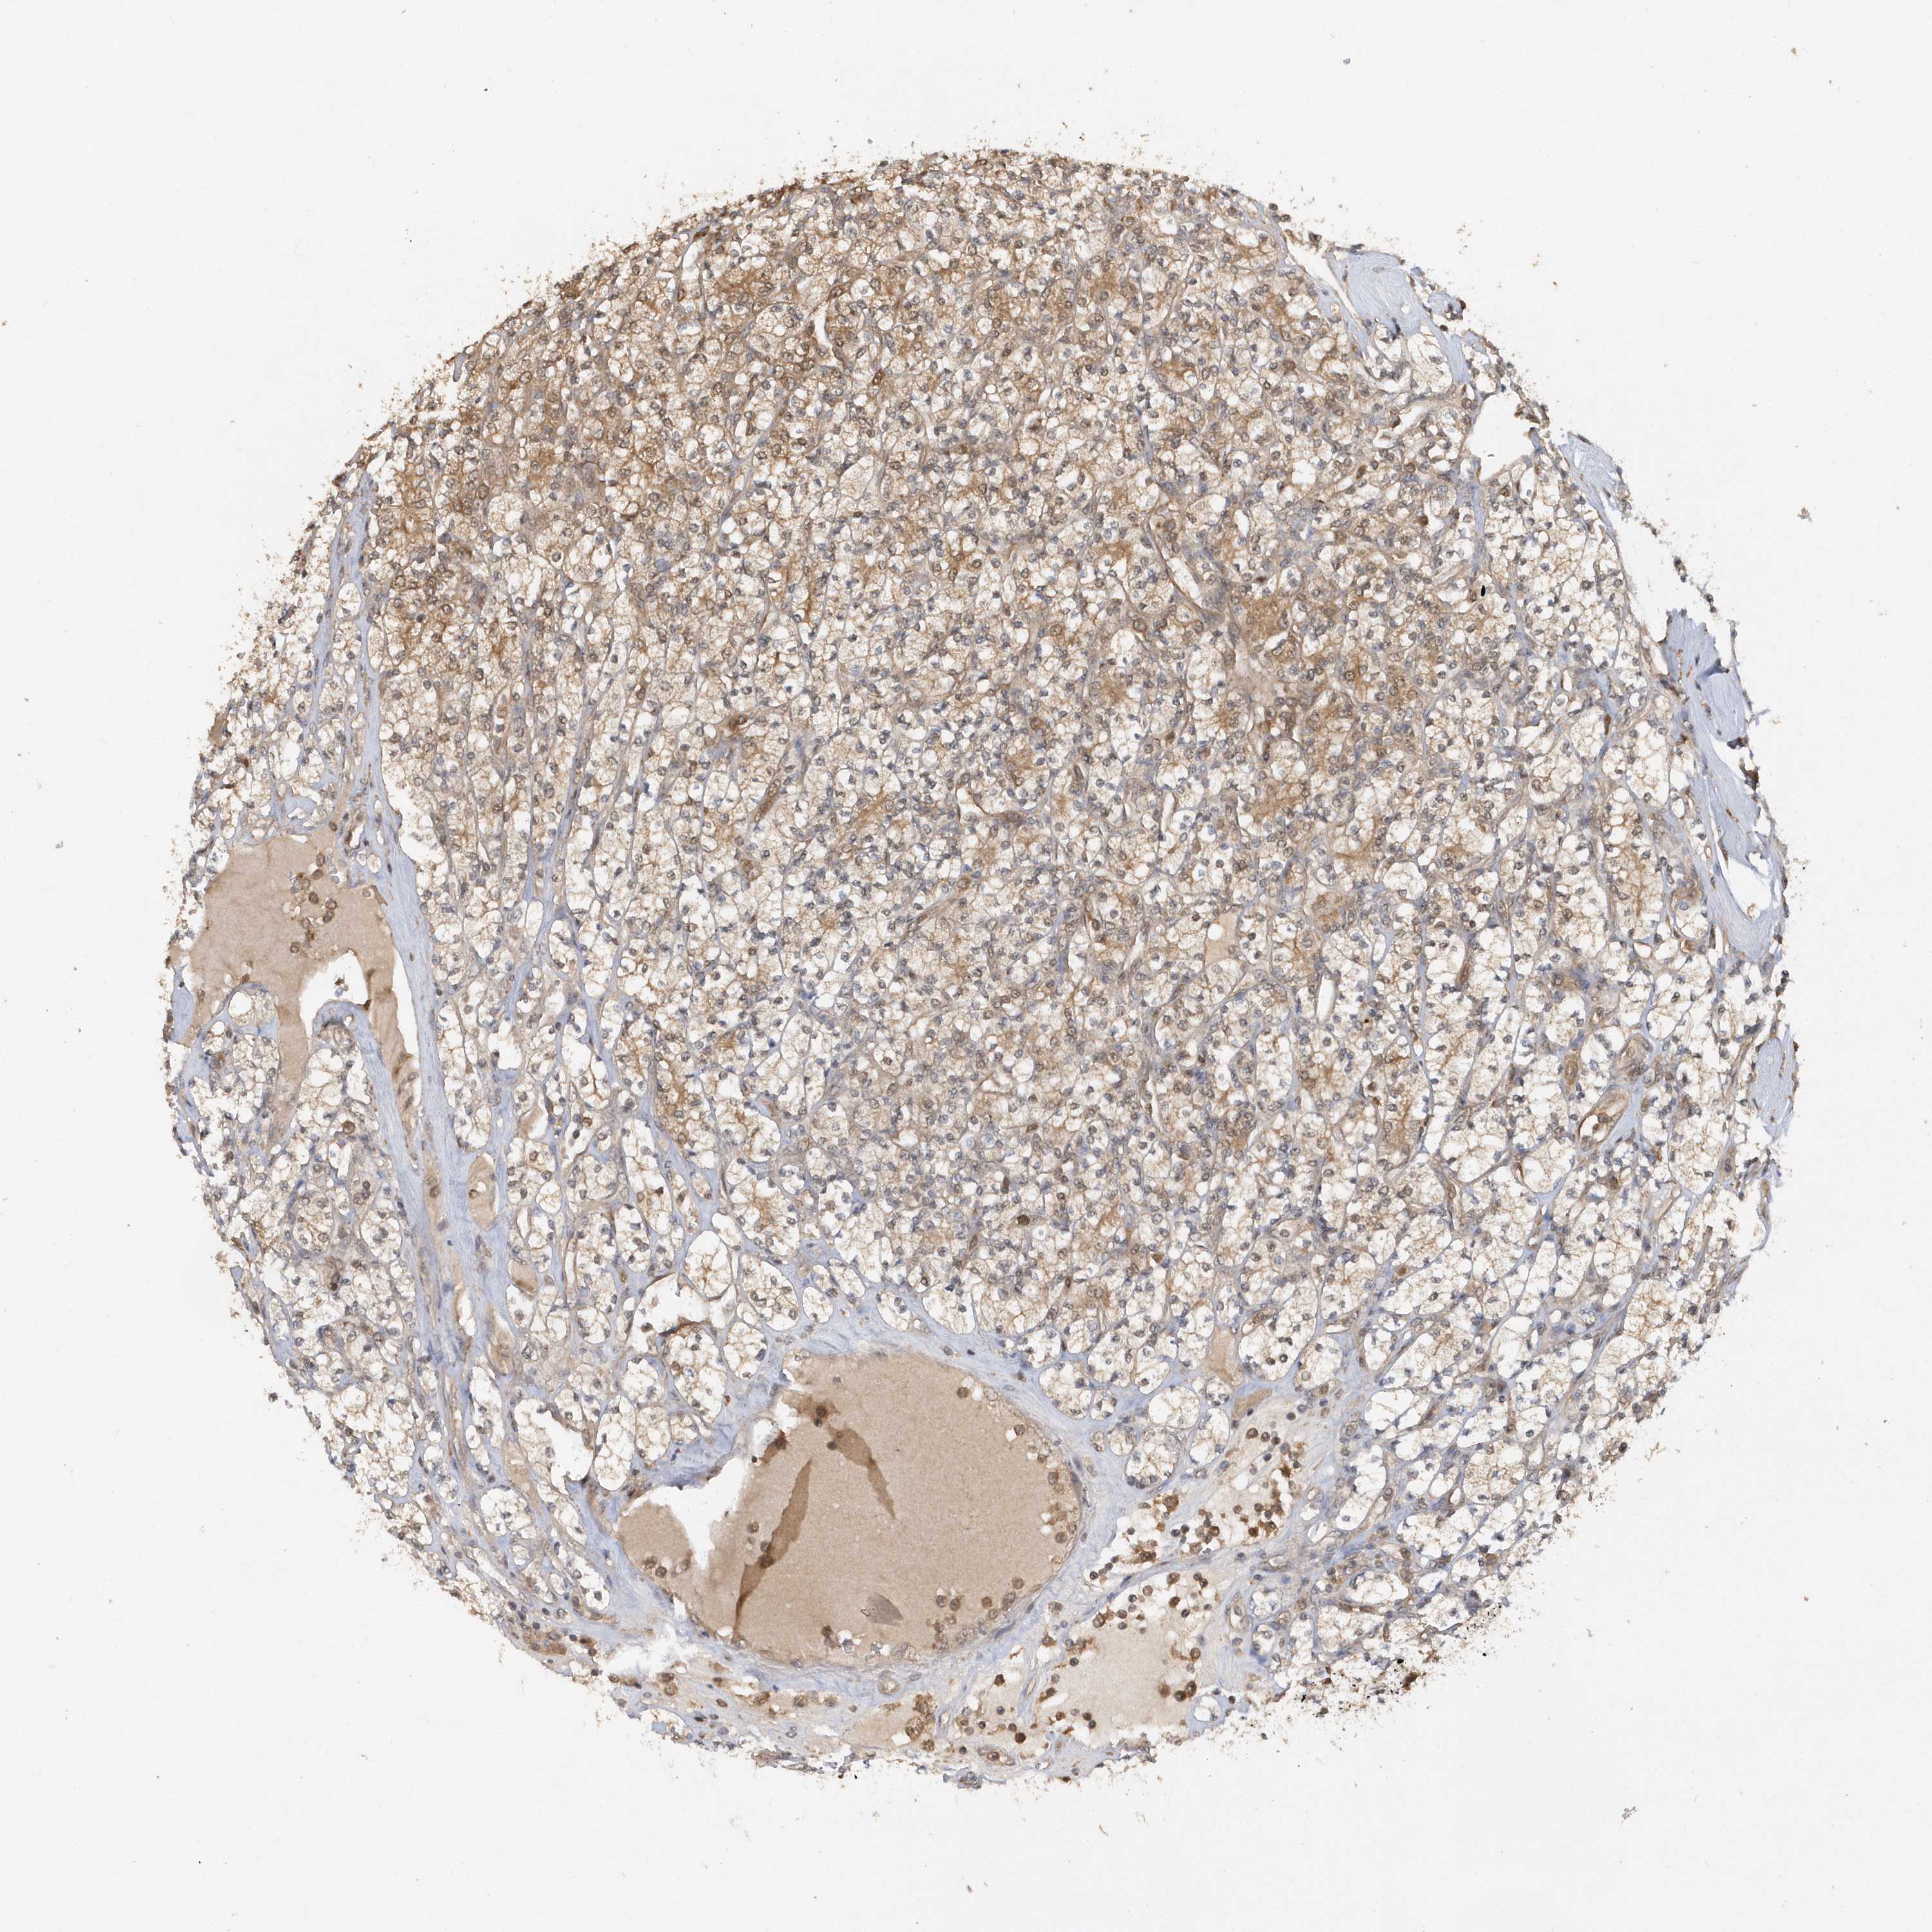

RPE is potential prognostic, high expression is favorable in Kidney Renal Clear Cell Carcinoma (TCGA)

Average pTPM 26.1

Number of samples 521